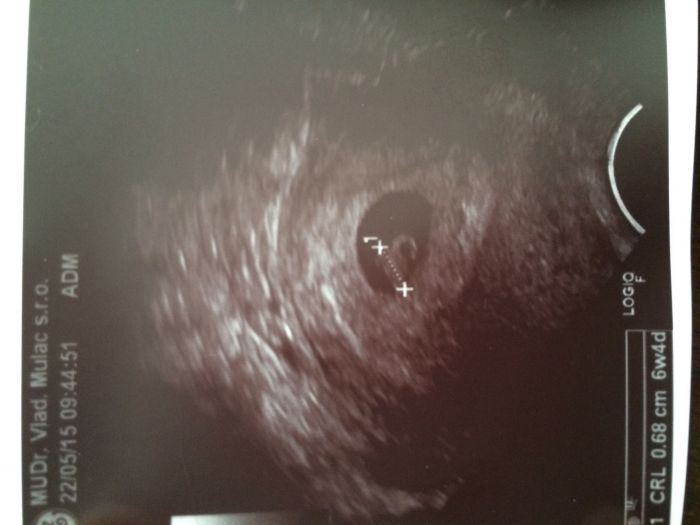

Autor: Anet   22.5.2015 v 17:46

Ahoj holky, taky prikladam z dneska fotecku. Můj výpočet dle menstruace na den odpovídá UTZ, tak jsem ráda. Srdíčko nám bije a všechno je, jak má. Mám i potvrzený datum porodu, 10.1. :)))